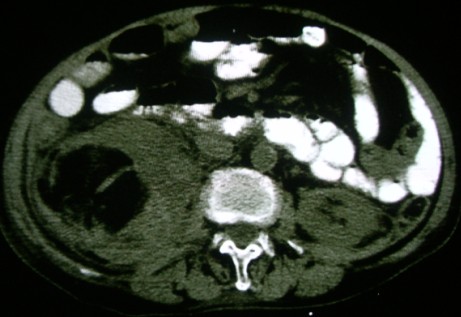

标题: CT6254:续前腹部CT肾脏病变

右侧肾脏内可见混杂密度,可见到低密度脂肪成分,1)右肾血管平滑肌脂肪瘤2)肾癌累积肾周脂肪.不过都要增强

支持:右肾血管平滑肌脂肪瘤伴出血。

右肾血管平滑肌脂肪瘤伴出血.

考虑:右肾血管平滑肌脂肪瘤,建议增强。

支持肾血管平滑肌脂肪瘤,应该比较典型.

右肾血管平滑肌脂肪瘤

右肾血管平滑肌脂肪瘤伴出血。

右肾错构瘤伴出血